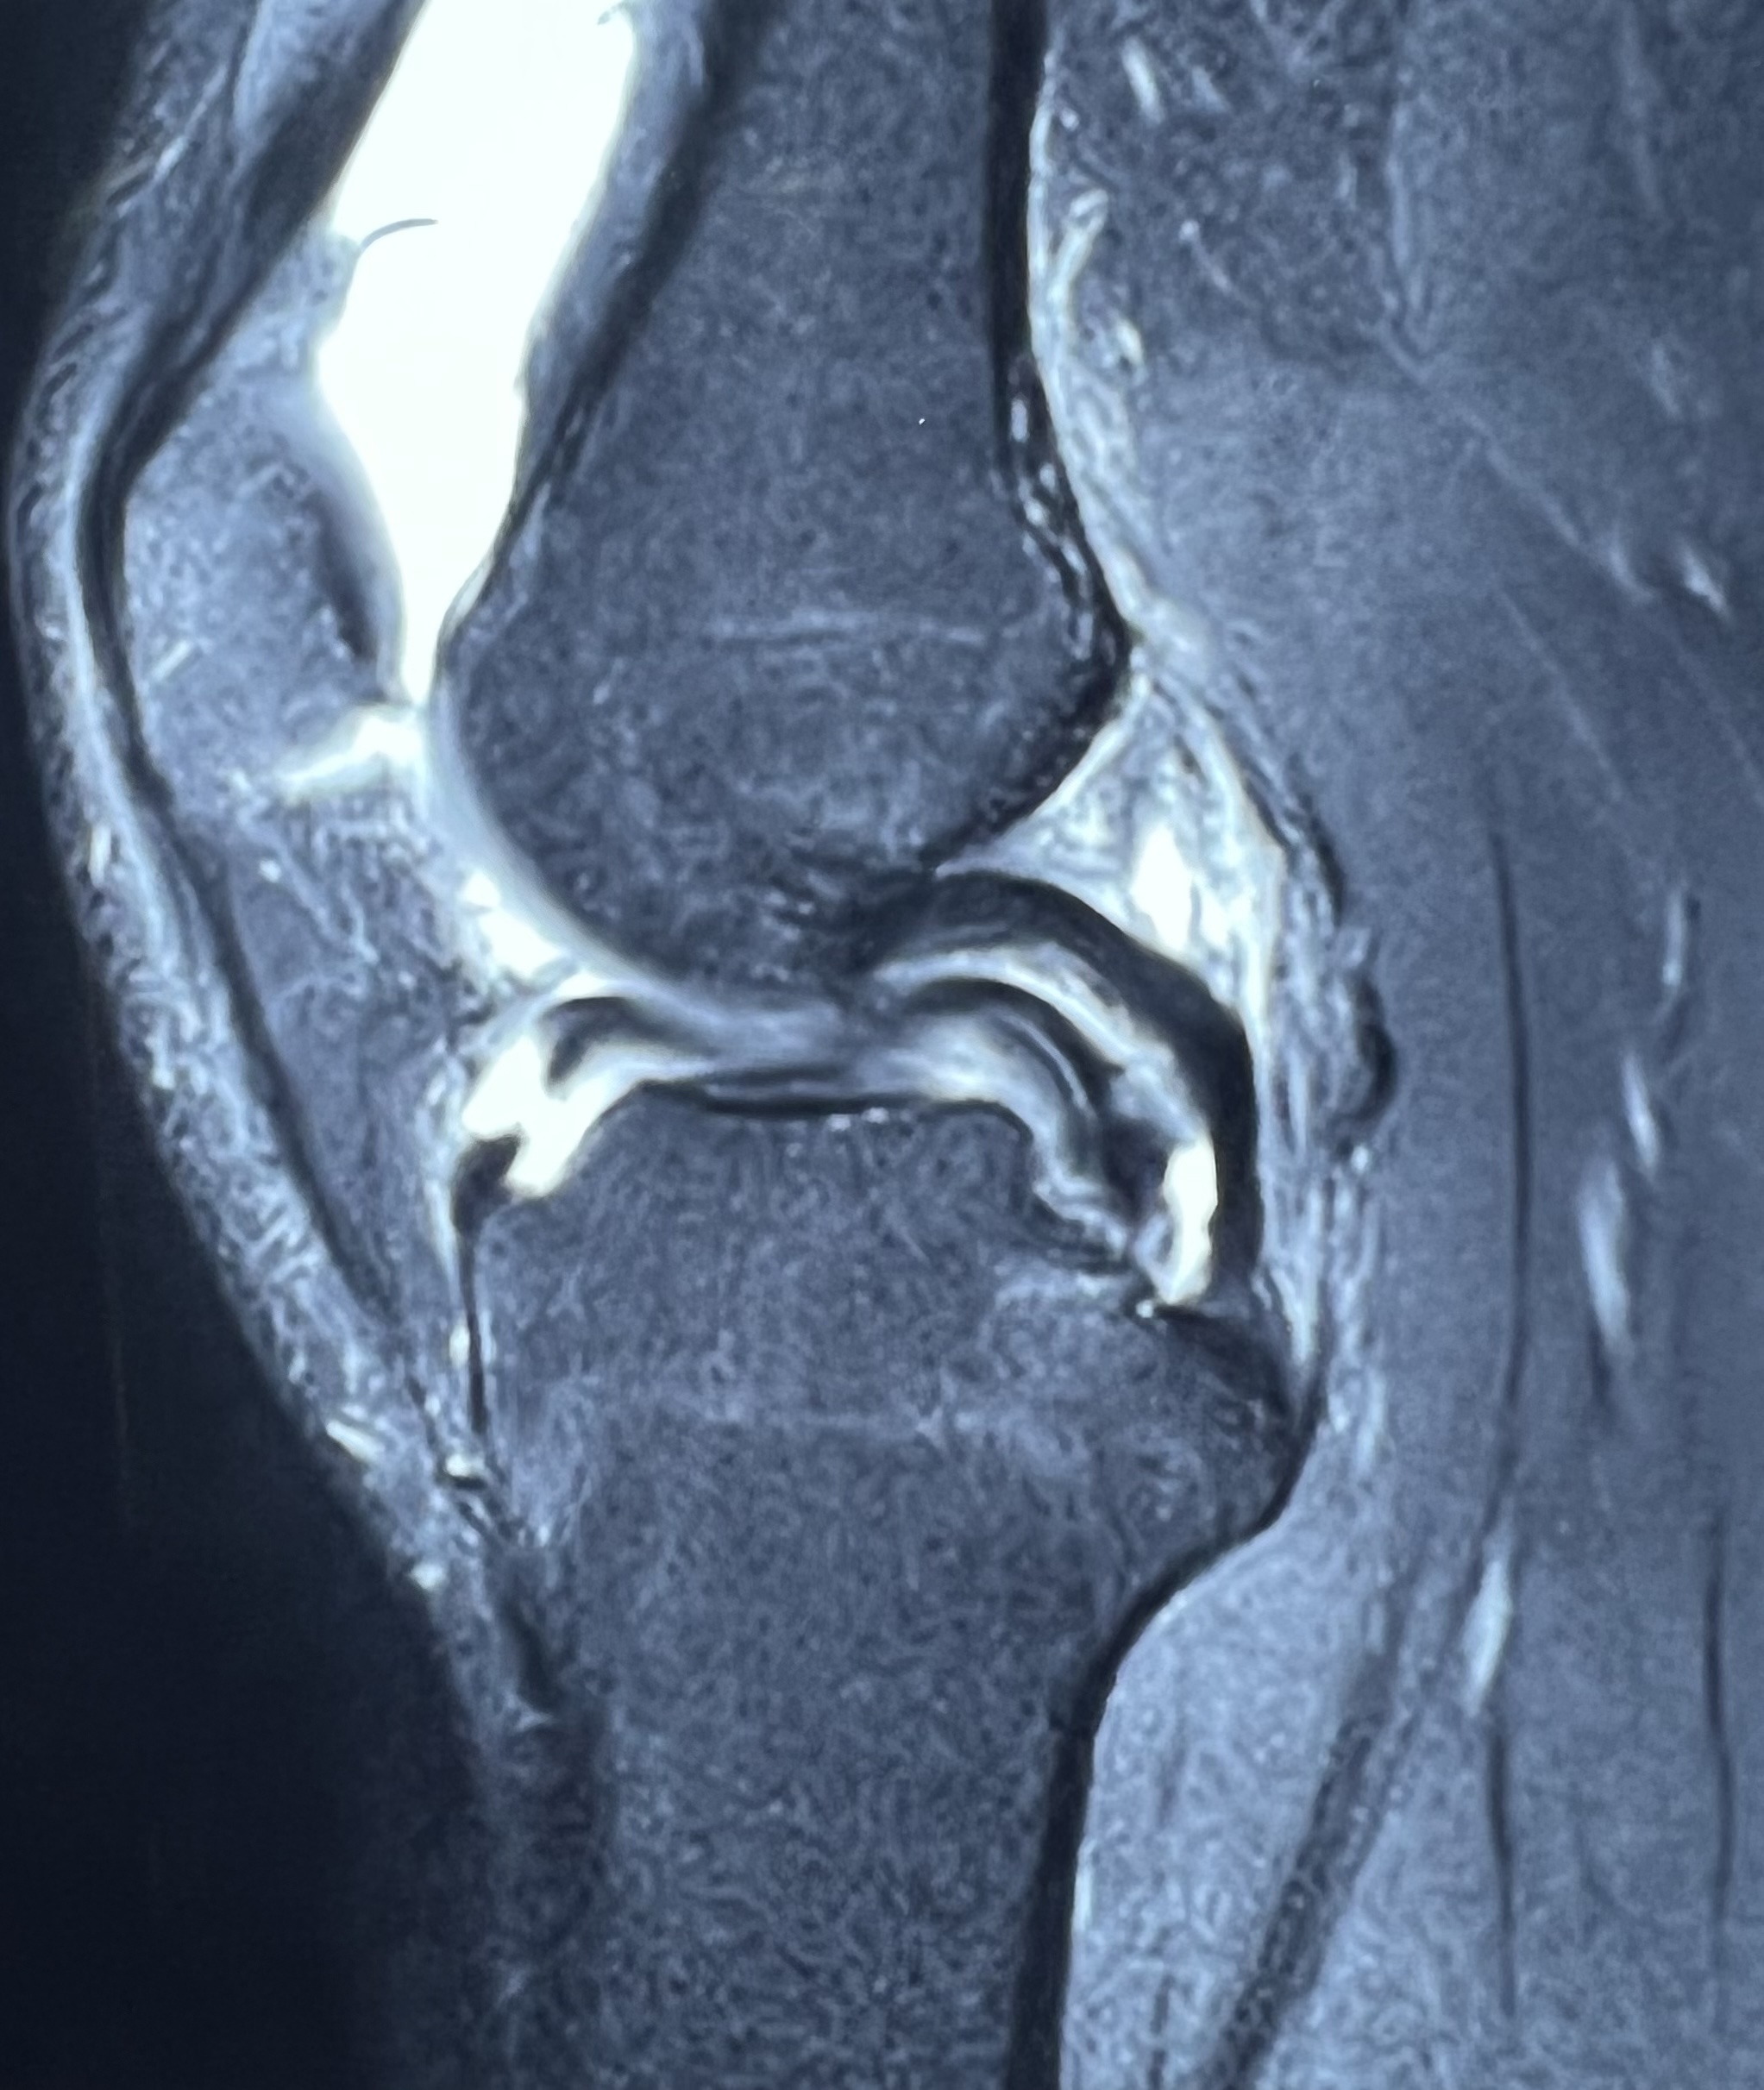

After ACL surgery, most patients can begin light jogging in about 3 months and progress to running by 6 months. However, recovery time can vary from person to person. Some patients may take longer if their thigh muscles are still weak or rehabilitation has not been adequate. If you are unable to run even after 7 months of ACL surgery, the possible reasons may include: Improper or incomplete rehabilitation exercises – Weak quadriceps and hamstring muscles can delay recovery. Loose or stretched ligament graft – This can affect knee stability and confidence while running. Failure of ACL surgery – In rare cases, the graft may not have healed properly. Associated knee problems – Meniscus or cartilage issues can also cause pain or instability. In such a situation, it is important to visit your orthopedic surgeon for a proper clinical examination. If required, your doctor may advise a 3 Tesla MRI scan to evaluate the condition of the ACL graft and bone tunnels. If the MRI shows that the graft and tunnels are normal, then focused physiotherapy and structured rehab can help you return to running. Working with a trained physiotherapist can make a big difference in regaining strength, balance, and confidence. I hope this information helps you understand the reasons and the right steps to take for a successful recovery.